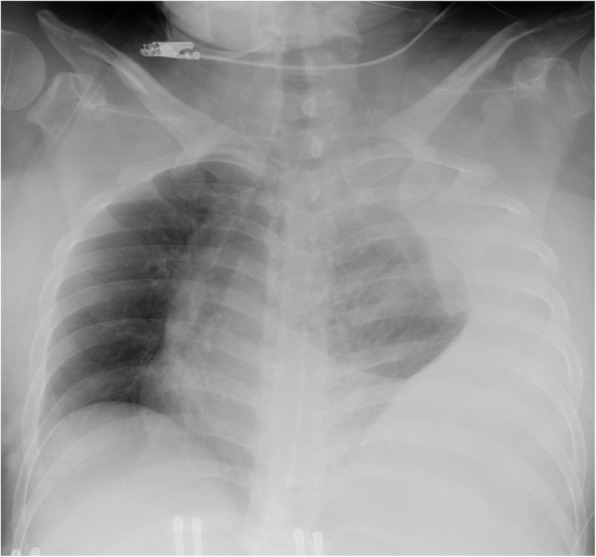

On arrival, she was conscious with a blood pressure of 110/90 mmHg and pulse rate of 90 beats/min. Her hemoglobin level was 10 g/dL and oxygen saturation was 97% with 10 L/min oxygen delivered via mask. Chest radiography revealed a massive left pleural effusion with left-to-right mediastinal shift (Fig. 1). Chest computed tomography (CT) revealed a left pleural effusion and irregularities of the left 10th intercostal artery (Fig. 2). We suspected hemothorax because the CT value of the effusion was 45 Hounsfield units. Furthermore, CT findings also implied intrathoracic dural ectasia close to the artery. A chest tube was inserted immediately; however, only 400 mL of old blood could be removed, and no further significant discharge was collected though the pleural effusion remained. The patient was hemodynamically stable following fluid resuscitation; however, the fetal heart rate was decreasing, and the fetus was in a critical condition. After obstetric consultation, we performed an immediate caesarean section under general anesthesia; the operative time was 40 min and the volume of blood lost including amniotic fluid was 300 mL.

Fig. 1.

Frontal chest radiograph showing massive left pleural fluid collection with a mediastinal shift to the right